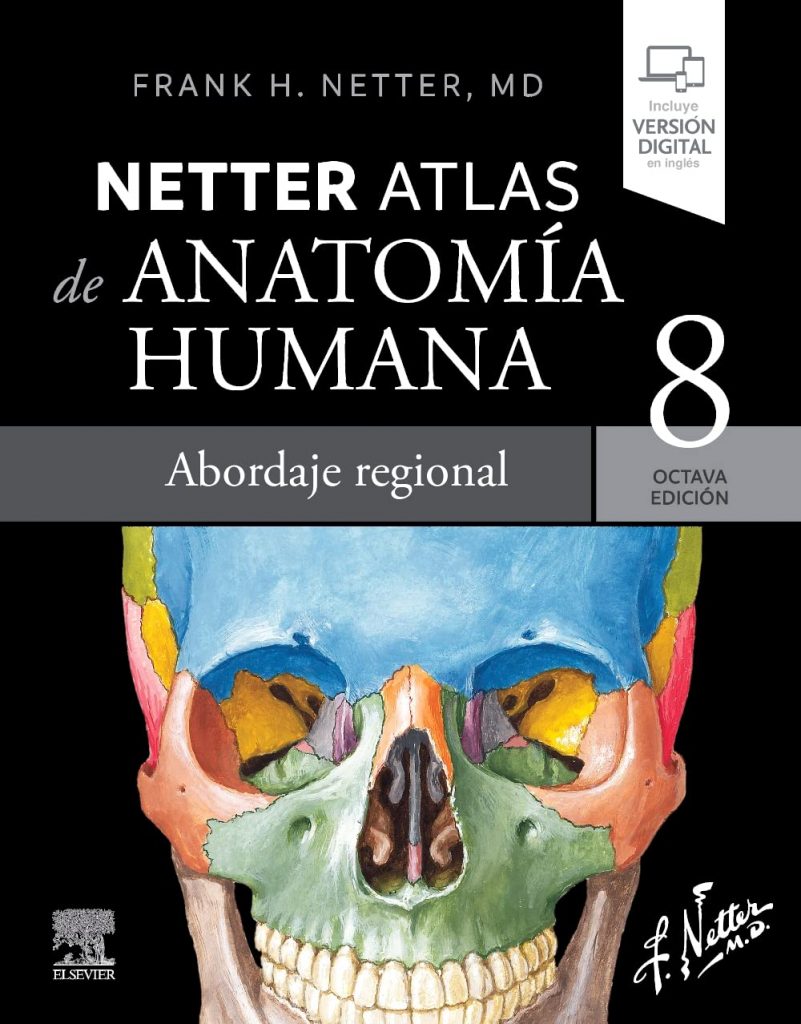

Opinión de Netter. Atlas de anatomía humana. Abordaje regional – Reseña completa y análisis profesional

Si estás buscando un atlas de anatomía “para estudiar de verdad” (no solo para mirar láminas bonitas), Netter. Atlas de anatomía humana. Abordaje regional sigue siendo una de las apuestas más seguras dentro de Ciencias de la Salud: ilustración extremadamente clara, foco en relaciones anatómicas útiles en clínica y una organización por regiones que encaja […]